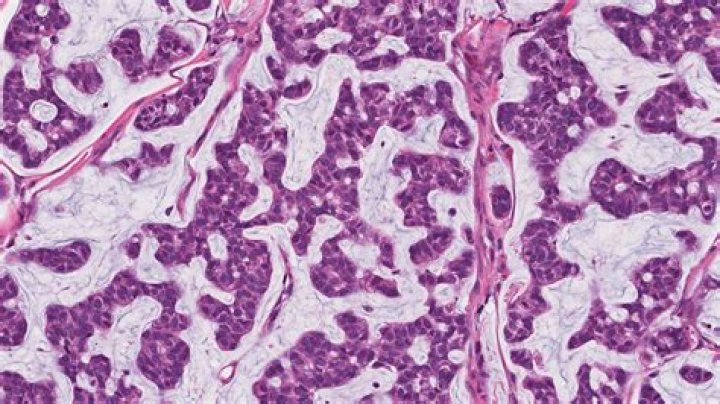

Mucins are high-molecular weight glycoproteins typically found in normal skin in small amounts. There are several reports regarding different types of cutaneous mucinosis. In this report, we discuss mucins in dermatopathology as a diagnostic clue of some well-known entities and some less frequent cutaneous diseases.

All involve accumulation in the skin of abnormal amounts of mucin. This is a jelly-like complex carbohydrate substance, called hyaluronic acid, that occurs normally as part of the connective tissue in the dermis or mid-layer of the skin. The abnormal deposits that occur in mucinoses can be localised or widespread.

Mucinous carcinoma is an invasive type of cancer that begins in an internal organ that produces mucin, the primary ingredient of mucus. The abnormal cells inside this type of tumor are floating in the mucin, and the mucin becomes a part of the tumor.

Follicular mucinosis is a rare cutaneous mucinosis characterized by accumulation of mucin at the external root sheath and sebaceous glands [1]. It manifests clinically as follicular papules distributed on the trunk, proximal limbs, scalp, and face; it may also exist as indurated plaques [2].